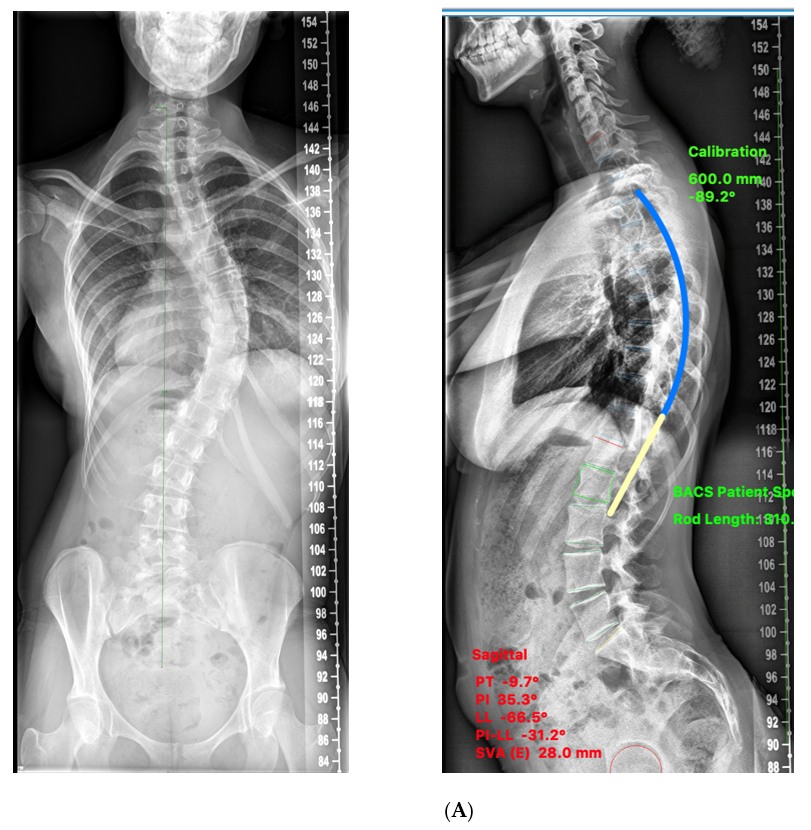

2. Materials and Methods